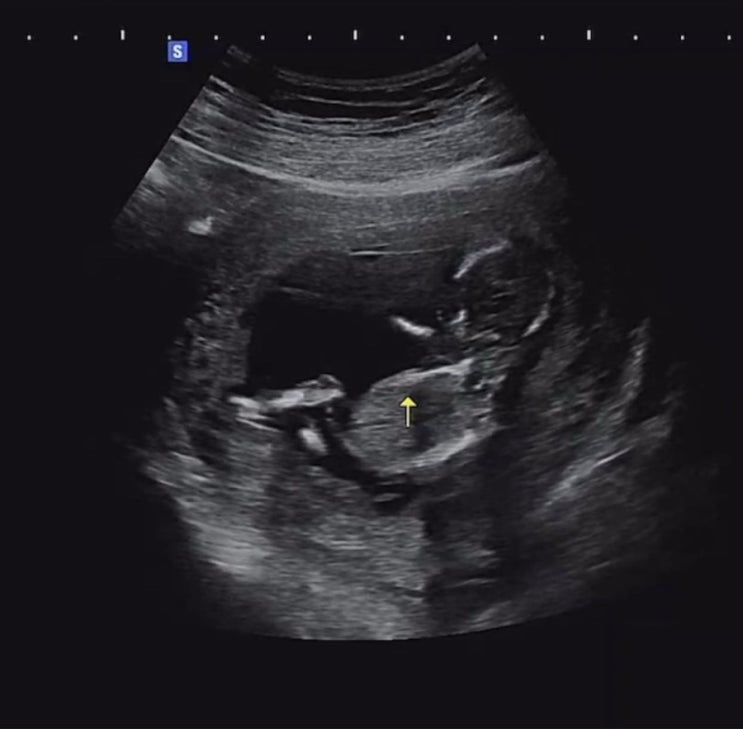

임신 13-18주차 : 아들일까 딸일까 ??❤️??